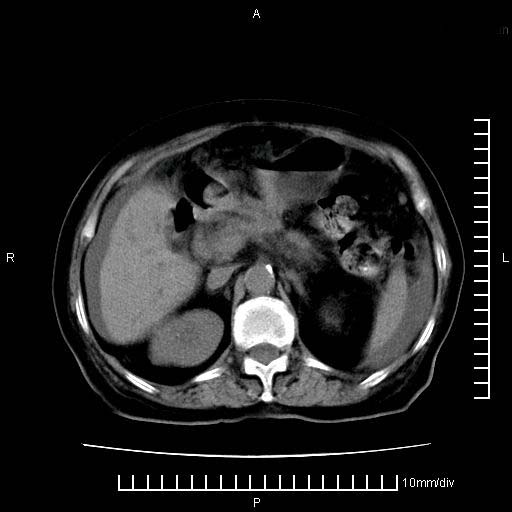

标题: CT28280:腹部增强:女性,80岁

上腹疼痛月余,外院核磁诊断胰腺癌。现临床示右下腹可明显触及包块,可片子上怎么没有看到?

1。胰腺ca伴腹膜腔转移

2。肝左叶低密度灶,考虑转移可能

支持胰腺癌肝内转移,腹水改变。

1、考虑胰腺癌伴腹膜腔转移,胸腹水。

2、肝脏转移可能。

考虑胰腺ca伴腹膜腔转移、肝左叶转移、右肾积水。右胸腔积液。